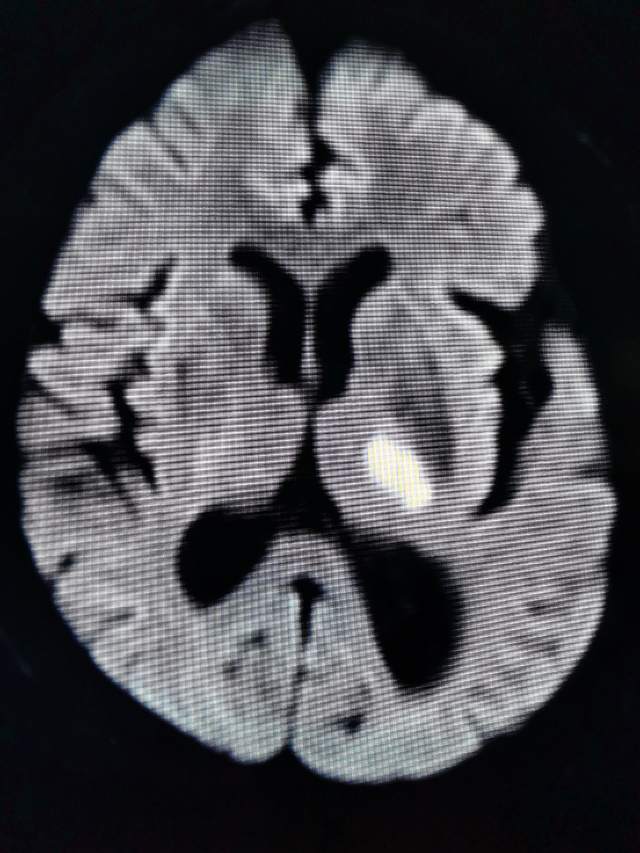

最近,老王突发右侧肢体活动障碍和言语不清,患者和家属都感觉有点离谱,立即送往医院,外院检查发现左侧侧脑室旁可见新鲜“脑梗塞”,血管似乎也可以,没啥明显的异常,保守治疗后无缓解。